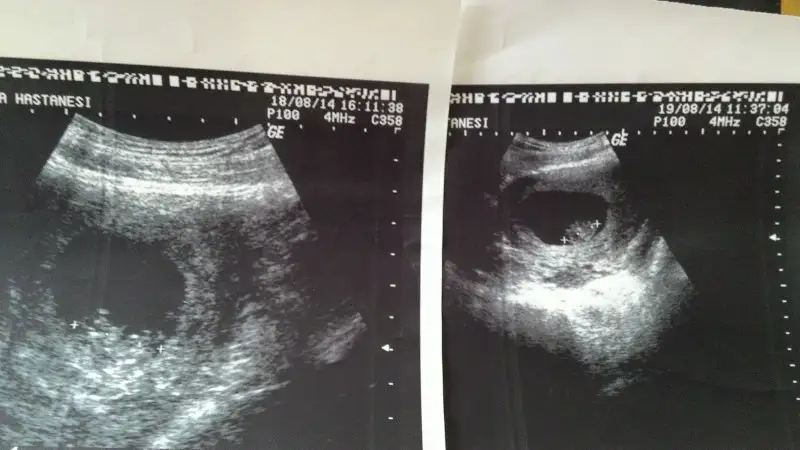

Bu da benim minis .. bakalım bende öğrenince yazarım..

doktorumuz dün cinsiyeti söylemiş olsaydı bu teori doğrumu değilmi söyleyebilirdim 16.haftadayım ama miniğim kızmı erkekmi bilmiyorumo zaman bu teoriye göre kız oluyo canım onu bebek sandım ben :)

Canım zaten % 85 ve senin bebek ortada, ne sağ ne sol..doktorumuz dün cinsiyeti söylemiş olsaydı bu teori doğrumu değilmi söyleyebilirdim 16.haftadayım ama miniğim kızmı erkekmi bilmiyorum